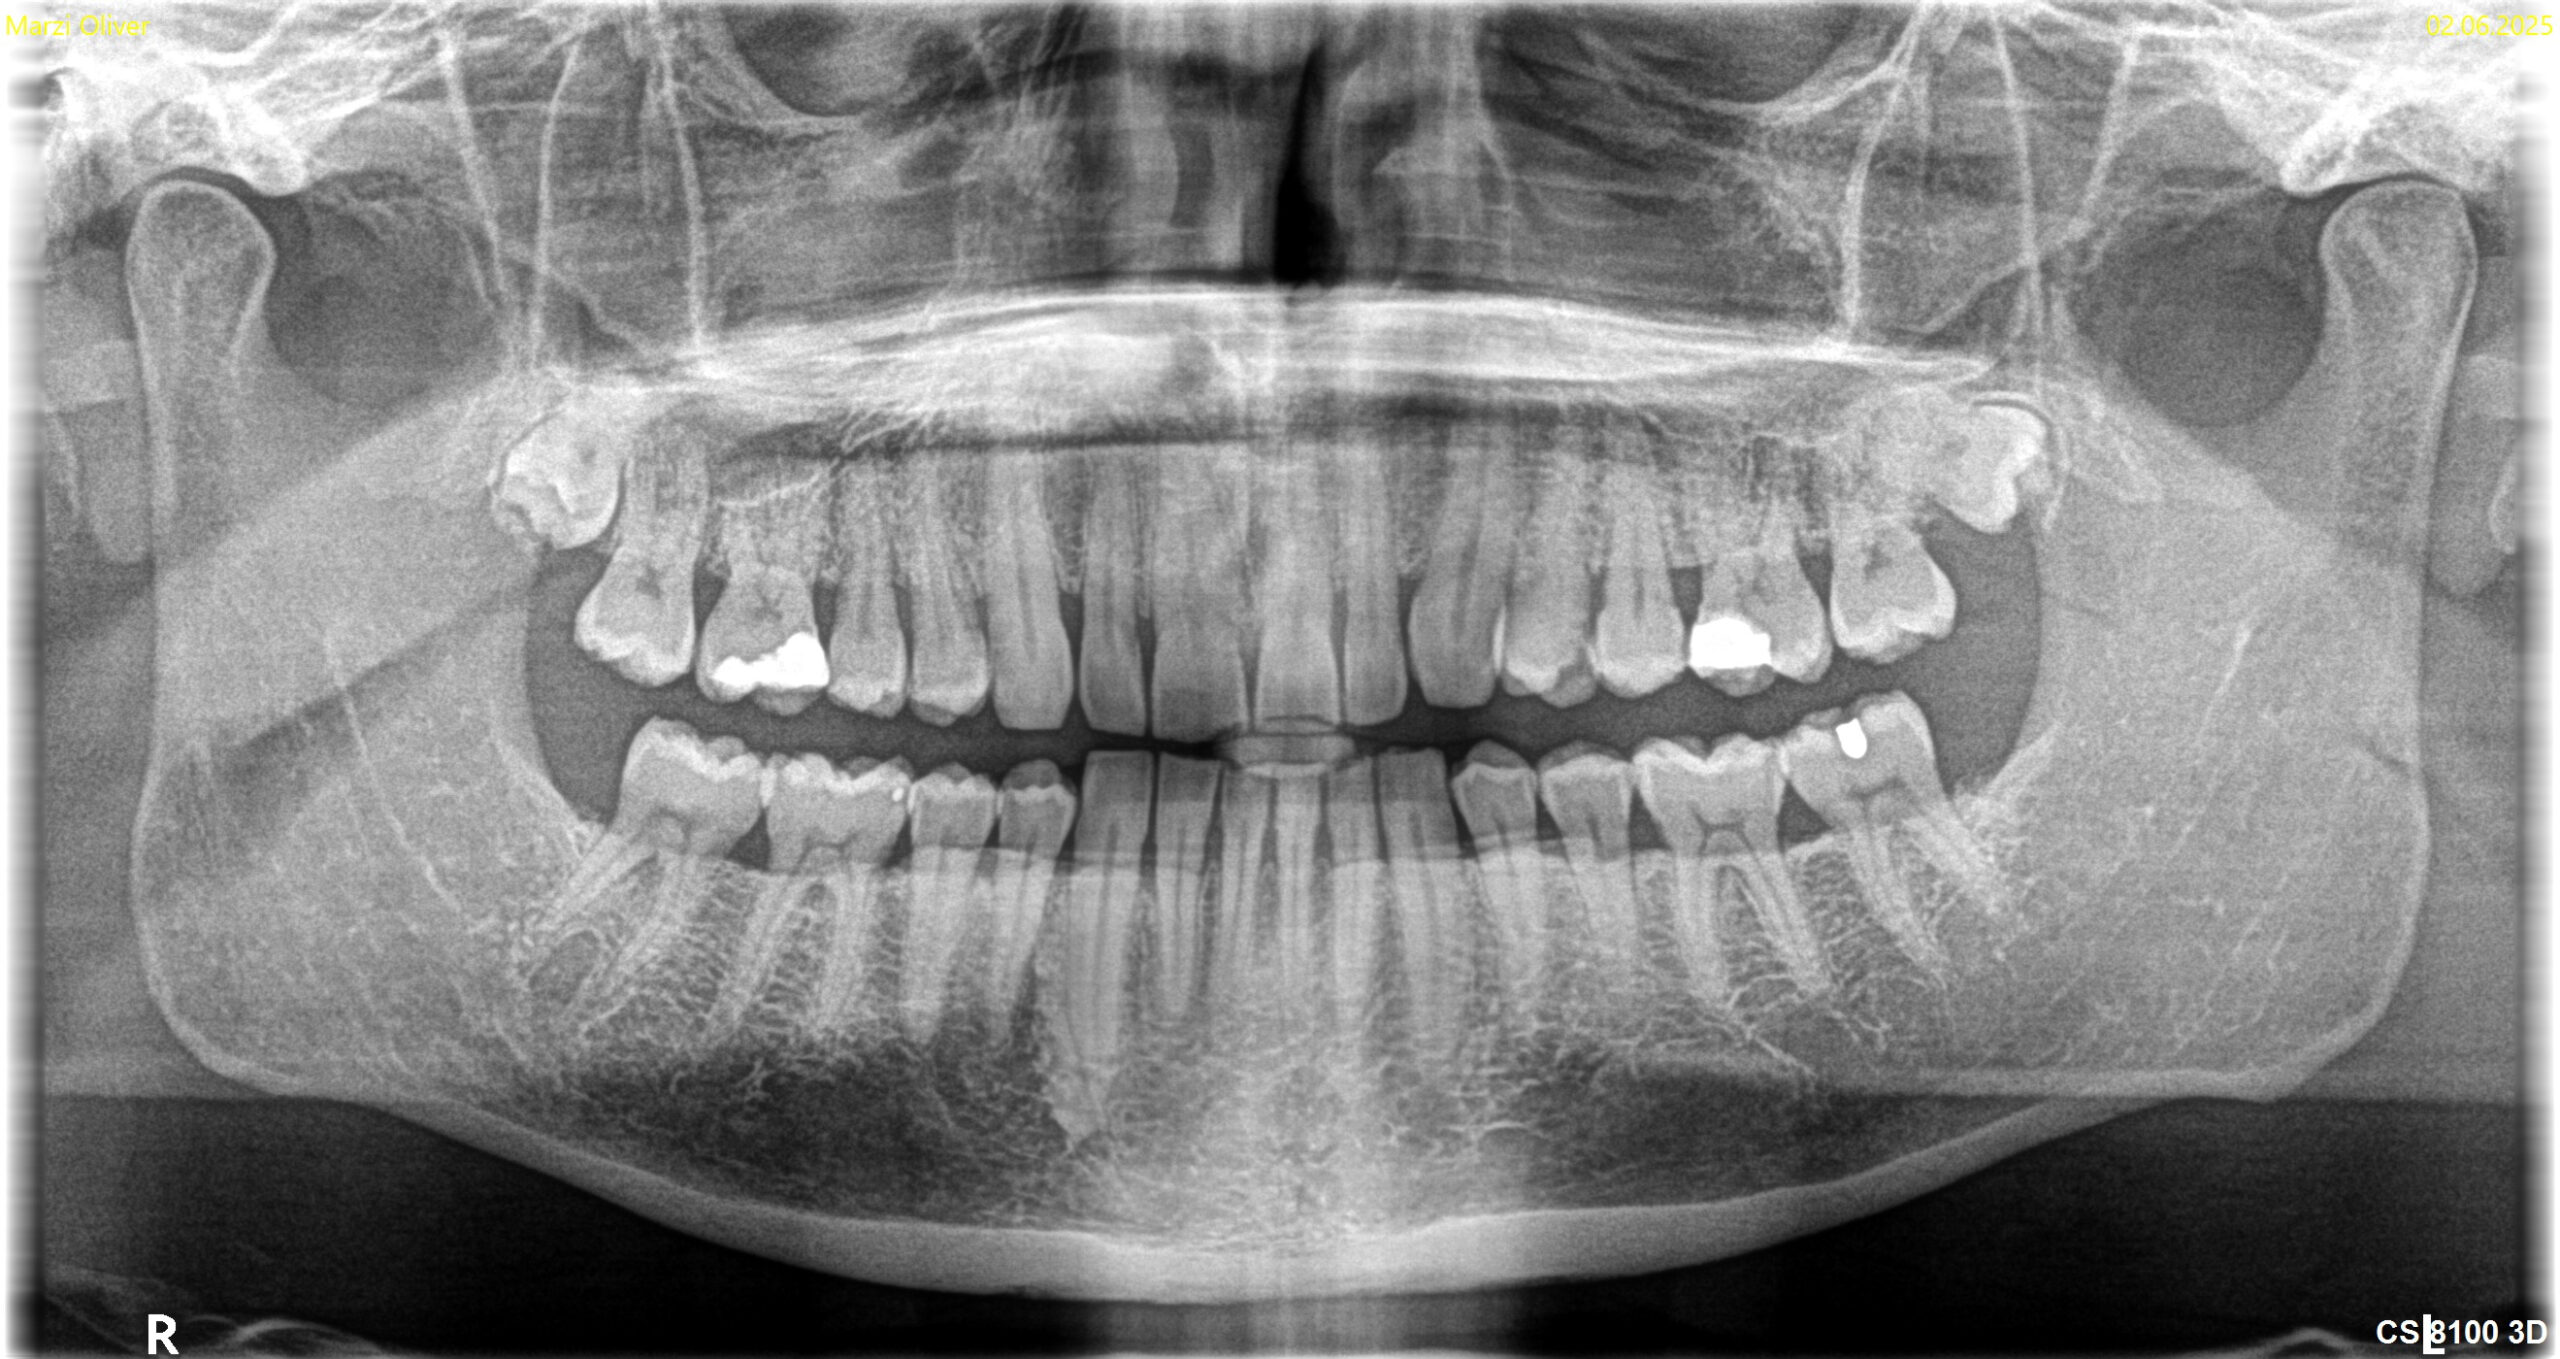

Das OPG ist eine Röntgen-Übersichtsaufnahme beider Kiefer. Der Name setzt sich zusammen aus „Ortho“ (gerade), „Pan“ (alles) und „Tomogramm“ (Schichtaufnahme). Die Aufnahme zeigt auf einem einzigen Bild sämtliche Zähne, beide Kieferknochen, die Kiefergelenke und Teile der Kieferhöhlen.

Bei Verdacht auf Parodontitis zeigt es, wo und wie viel Knochen bereits abgebaut wurde. Der Zahnarzt erkennt, ob der Abbau horizontal verläuft (gleichmäßig entlang der Zahnreihe) oder vertikal (trichterförmig an einzelnen Zähnen). Diese Information ist wichtig für die Prognose und die Behandlungsplanung. Auch versteckte Entzündungen an Wurzelspitzen, verlagerte Weisheitszähne oder Zysten werden sichtbar. Implantate sind ebenfalls gut zu beurteilen.

Die Bildqualität reicht für die meisten Fragestellungen aus. Für Details an einzelnen Zähnen sind jedoch Zahnfilme (Einzelaufnahmen) überlegen, da sie eine höhere Auflösung bieten und Überlagerungen vermeiden. Bei komplexen chirurgischen Planungen, etwa vor Implantationen, kann ein dreidimensionales DVT (digitale Volumentomografie) sinnvoll sein.